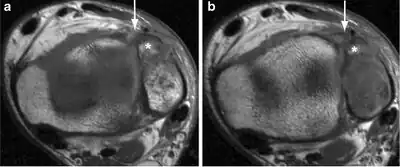

| a, b)Image demonstrates the avulsion fracture of the anterior aspect of the fibula (Wagstaffe–Lefort, asterisk), with a discontinuous aspect of the anterior distal tibiofibular ligament | |

Le Fort's fracture of the ankle is a vertical fracture of the antero-medial part of the distal fibula with avulsion of the anterior tibiofibular ligament,[1] opposite to a Tillaux-Chaput avulsion fracture